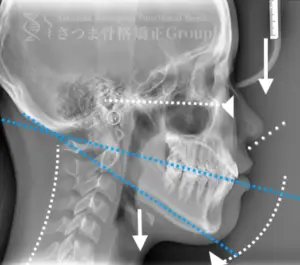

レントゲン分析による精密な骨格評価

渋谷TMJ歯科クリニックでは、提携先である「さつま骨格矯正」の施術効果を高めるため、レントゲン写真(X-ray images)の撮影を行っています。

顎関節や頭蓋骨、頸椎の位置関係を明確にすることで、施術前の状態を正確に把握できます。

撮影したレントゲン写真は、さつま骨格矯正にて詳細に分析され、施術計画の立案に活用されます。

施術の前後で撮影したレントゲン写真を比較することで、改善の度合いや変化を一目で確認できます。